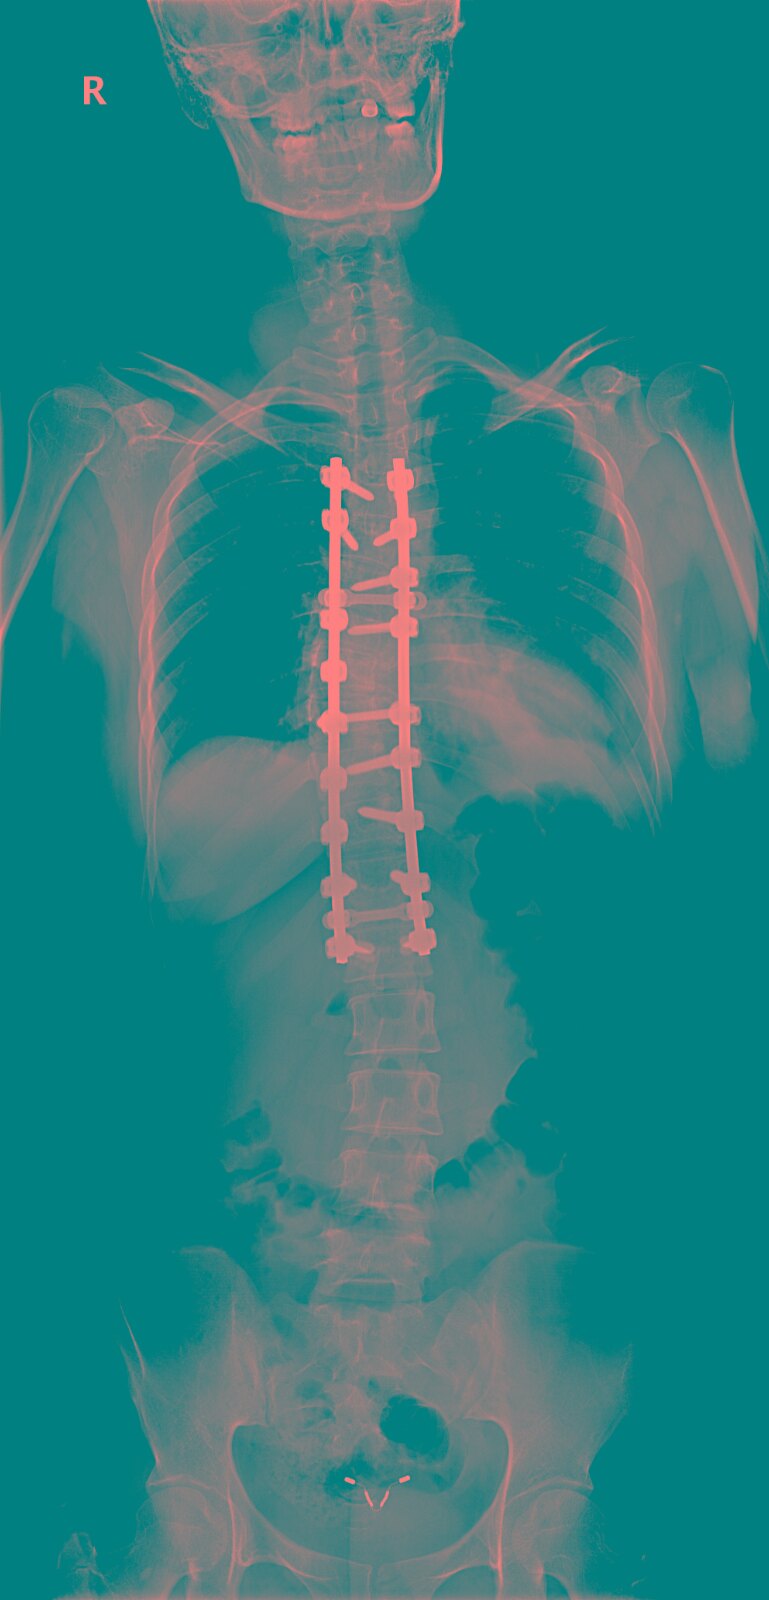

胸椎正侧位x线:提示胸8,9骨折脱位,胸5,6,7椎体骨折.

2,t10椎体压缩性骨折;1,t8-9椎体爆裂性骨折;我院胸椎ct及磁共振检查

术前检查:同时存在t2蝴蝶椎及t3半椎体畸形.

术前三维ct重建术前检查:同时存在t2蝴蝶椎及t3半椎体畸形.